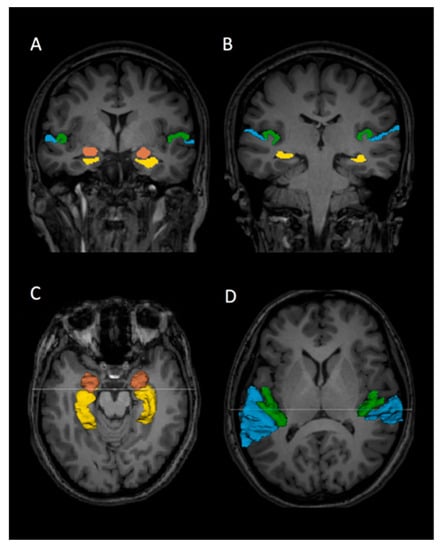

2.3. Regions of Interest and Volume Measurement